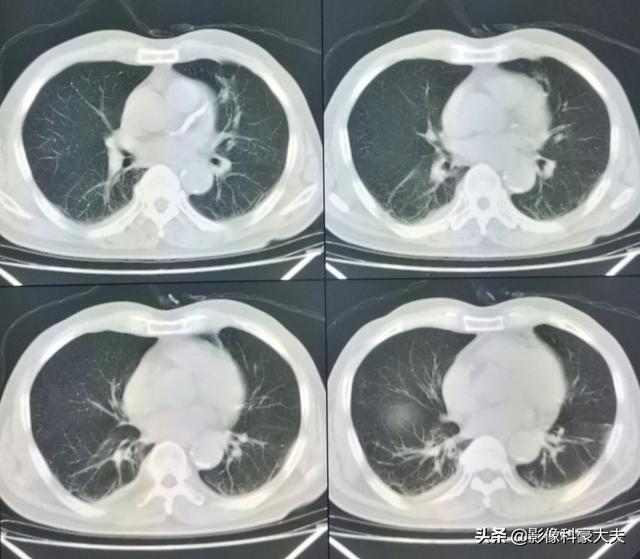

左肺にあるこの不規則な結節が原発巣で、わずか2.6cmしかない。このような骨転移を伴う肺がんは、もはや手術不可能です。肺がんはあまりにもありふれた病気であり、初期症状の中には非典型的なものや無症状のものさえあるからだ。肺がんの約30%では、転移の症状が最初の症状であり、さらなる肺がんが発見される前に転移が最初に発見される。

幸いこの患者は治療に敏感で、化学療法と標的療法に基づく治療を組み合わせて5年間治療を受けてきた。

直近のCT検査の結果、原発巣はかなり縮小しており、5年以上保菌したまま生きられたのは幸運だった!